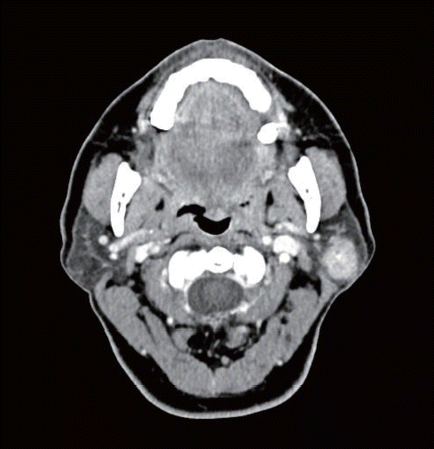

58세 여환에서 좌측 이하선 천엽에 국한된 2 cm 고형성 종괴가 관찰되었다. 이하선 천엽절제술 시행 후 조직검사상 선방세포암종(acinic cell carcinoma)으로 확인되었다. 절제연에서 종양은 관찰되지 않았으며 영상검사상 전이로 의심되는 소견은 관찰되지 않았다. 향후 치료를 위한 적절한 조치는?

① 추가 치료 없이 추적 관찰

② 이하선 심엽 절제술

③ 방사선 치료

④ 동시항암 방사선 치료

⑤ 예방적 경부 절제술

답 ①

이하선 천엽에서 발생한 초기의 저악성도 얌종에서는 이하선천엽절제술을 시행한다.